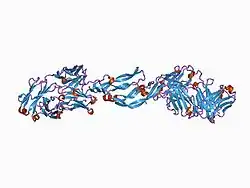

This gene is a member of the platelet-derived growth factor (PDGF)/vascular endothelial growth factor (VEGF) family and encodes a protein that is often found as a disulfide linked homodimer. This protein is a glycosylated mitogen that specifically acts on endothelial cells and has various effects, including mediating increased vascular permeability, inducing angiogenesis, vasculogenesis, and endothelial cell growth, promoting cell migration, and inhibiting apoptosis. Alternatively spliced transcript variants, encoding either freely secreted or cell-associated isoforms, have been characterized.[6]

Vascular endothelial growth factor A (VEGF-A) is a dimeric glycoprotein that plays a significant role in neurons and is considered to be the main, dominant inducer of the growth of blood vessels. VEGFA is essential for adults during organ remodeling and diseases that involve blood vessels, for example, in wound healing, tumor angiogenesis, diabetic retinopathy, and age-related macular degeneration. During early vertebrate development, vasculogenesis occurs which means that the endothelial condense into the blood vessels. The differentiation of endothelial cells is dependent upon the expression of VEGFA and if the expression is abolished then it can result in the death of the embryo. VEGFA is produced by a group of three major isoforms as a result of alternative splicing and if any three isoforms are produced (VEGFA120, VEGFA164, and VEGFA188) then this will not result in vessel defects and death of the full VEGFA knockout in mice. VEGFA is essential in the role of neurons because they too need vascular supply and abolishing the expression of VEGFA from neural progenitors will result in defects of the brain vascularization and neuronal apoptosis. Anti-VEGFA therapy can be used to treat patients with undesirable angiogenesis and vascular leakage in cancer and eye diseases but also could result in the inhibition of neurogenesis and neuroprotection. VEGFA could be used to treat patients with neurodegenerative and neuropathic conditions and also increase vascular permeability which will stop the blood-brain barrier and increase inflammatory cell infiltration.[7][8][9]